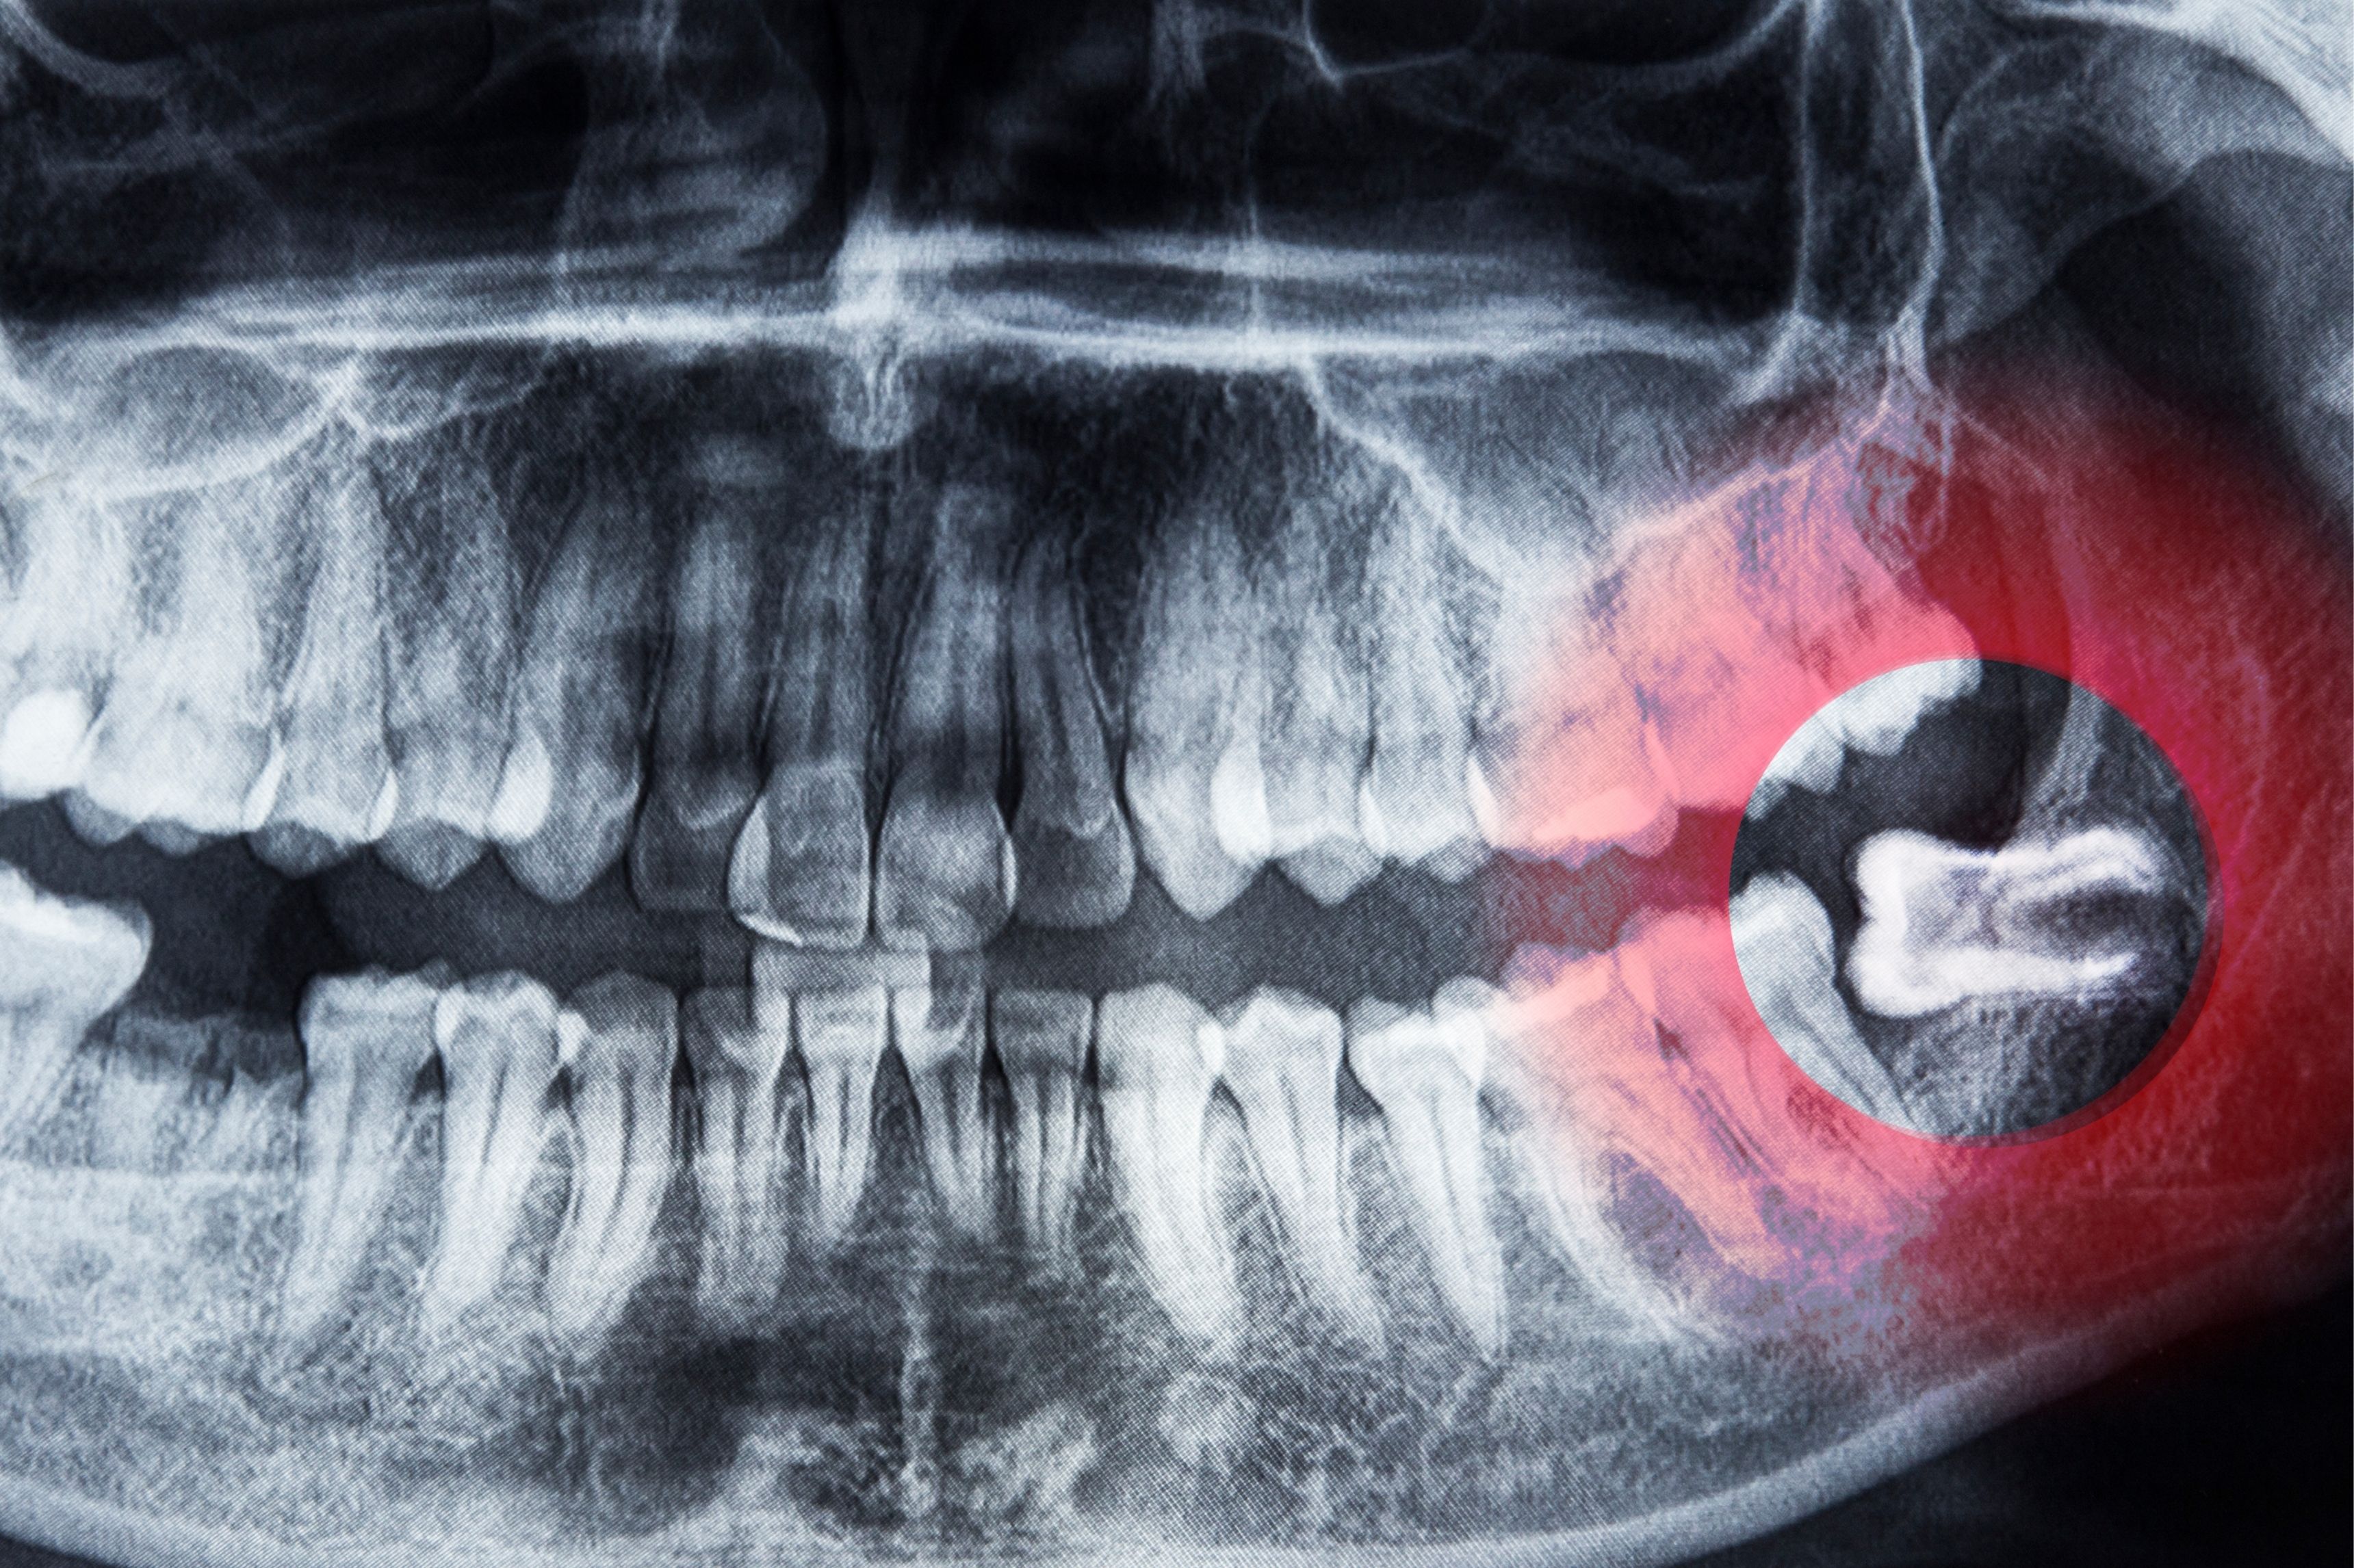

Răng khôn mọc lệch hàm dưới là tình trạng khá phổ biến, thường gây đau, viêm nướu, kẹt thức ăn hoặc thậm chí ảnh hưởng đến răng bên cạnh. Trong nhiều trường hợp, bác sĩ sẽ chỉ định nhổ răng để tránh biến chứng như nhiễm trùng hoặc tổn thương xương hàm.

Về chi phí, việc nhổ răng khôn mọc lệch sẽ phụ thuộc vào mức độ lệch, vị trí răng (mọc ngầm hay mọc một phần), độ khó của ca nhổ và cơ sở y tế bạn lựa chọn.